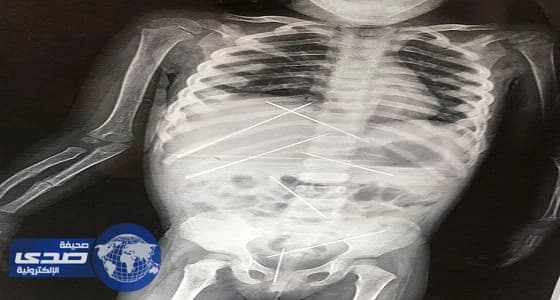

صورا مروعة لأشعة سينية تظهر ما لا يقل عن سبع إبر طويلة داخل بطن الطفلة، حيث قالت والدة الطفلة إن الإبر كانت داخل جسدها لمدة تتراوح بين 15 و20 يوما.

وقال الأطباء إنهم لم يتمكنوا من استخراج الإبر لعدم إلحاق الضرر بجسد الطفلة، وأبقوها تحت الملاحظة لمدة يومين حتى تستقر حالتها ، فيما تمكنت الشرطة الهندية من ضبط المتهم .